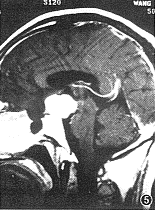

3. MR图像分析(图4~6):27例肿瘤位于鞍上,8例位于鞍上和(或)鞍内,4例长入桥前池,14例压迫大脑脚,2例压迫脑干,14例长入第3脑室,17例有脑积水,所有病例均未见有视神经增粗,鞍底正常3例、变平18例、下陷14例。肿瘤的最大径15~56 mm,平均34 mm。35例均可见有正常垂体,无肿瘤包绕蛛网膜下腔中血管的情况。肿瘤呈圆形或类圆形10例,边缘不规则形或分叶状25例。

图4,5 实性鳞状乳头型颅咽管瘤。图4为矢状面T1WI,示鞍上一类圆形等信号肿块影,肿瘤向后上方生长,鞍内垂体信号清晰可见。图5为矢状面增强扫描,显示病变明显均匀强化